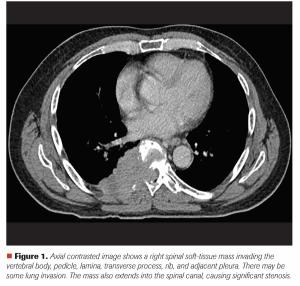

Mehmet S. Copur, MD, and colleagues examine the case of a 65-year-old who presented with back pain and a large T8 spinal mass, leading to a diagnosis of multiple myeloma with spinal cord compromise.